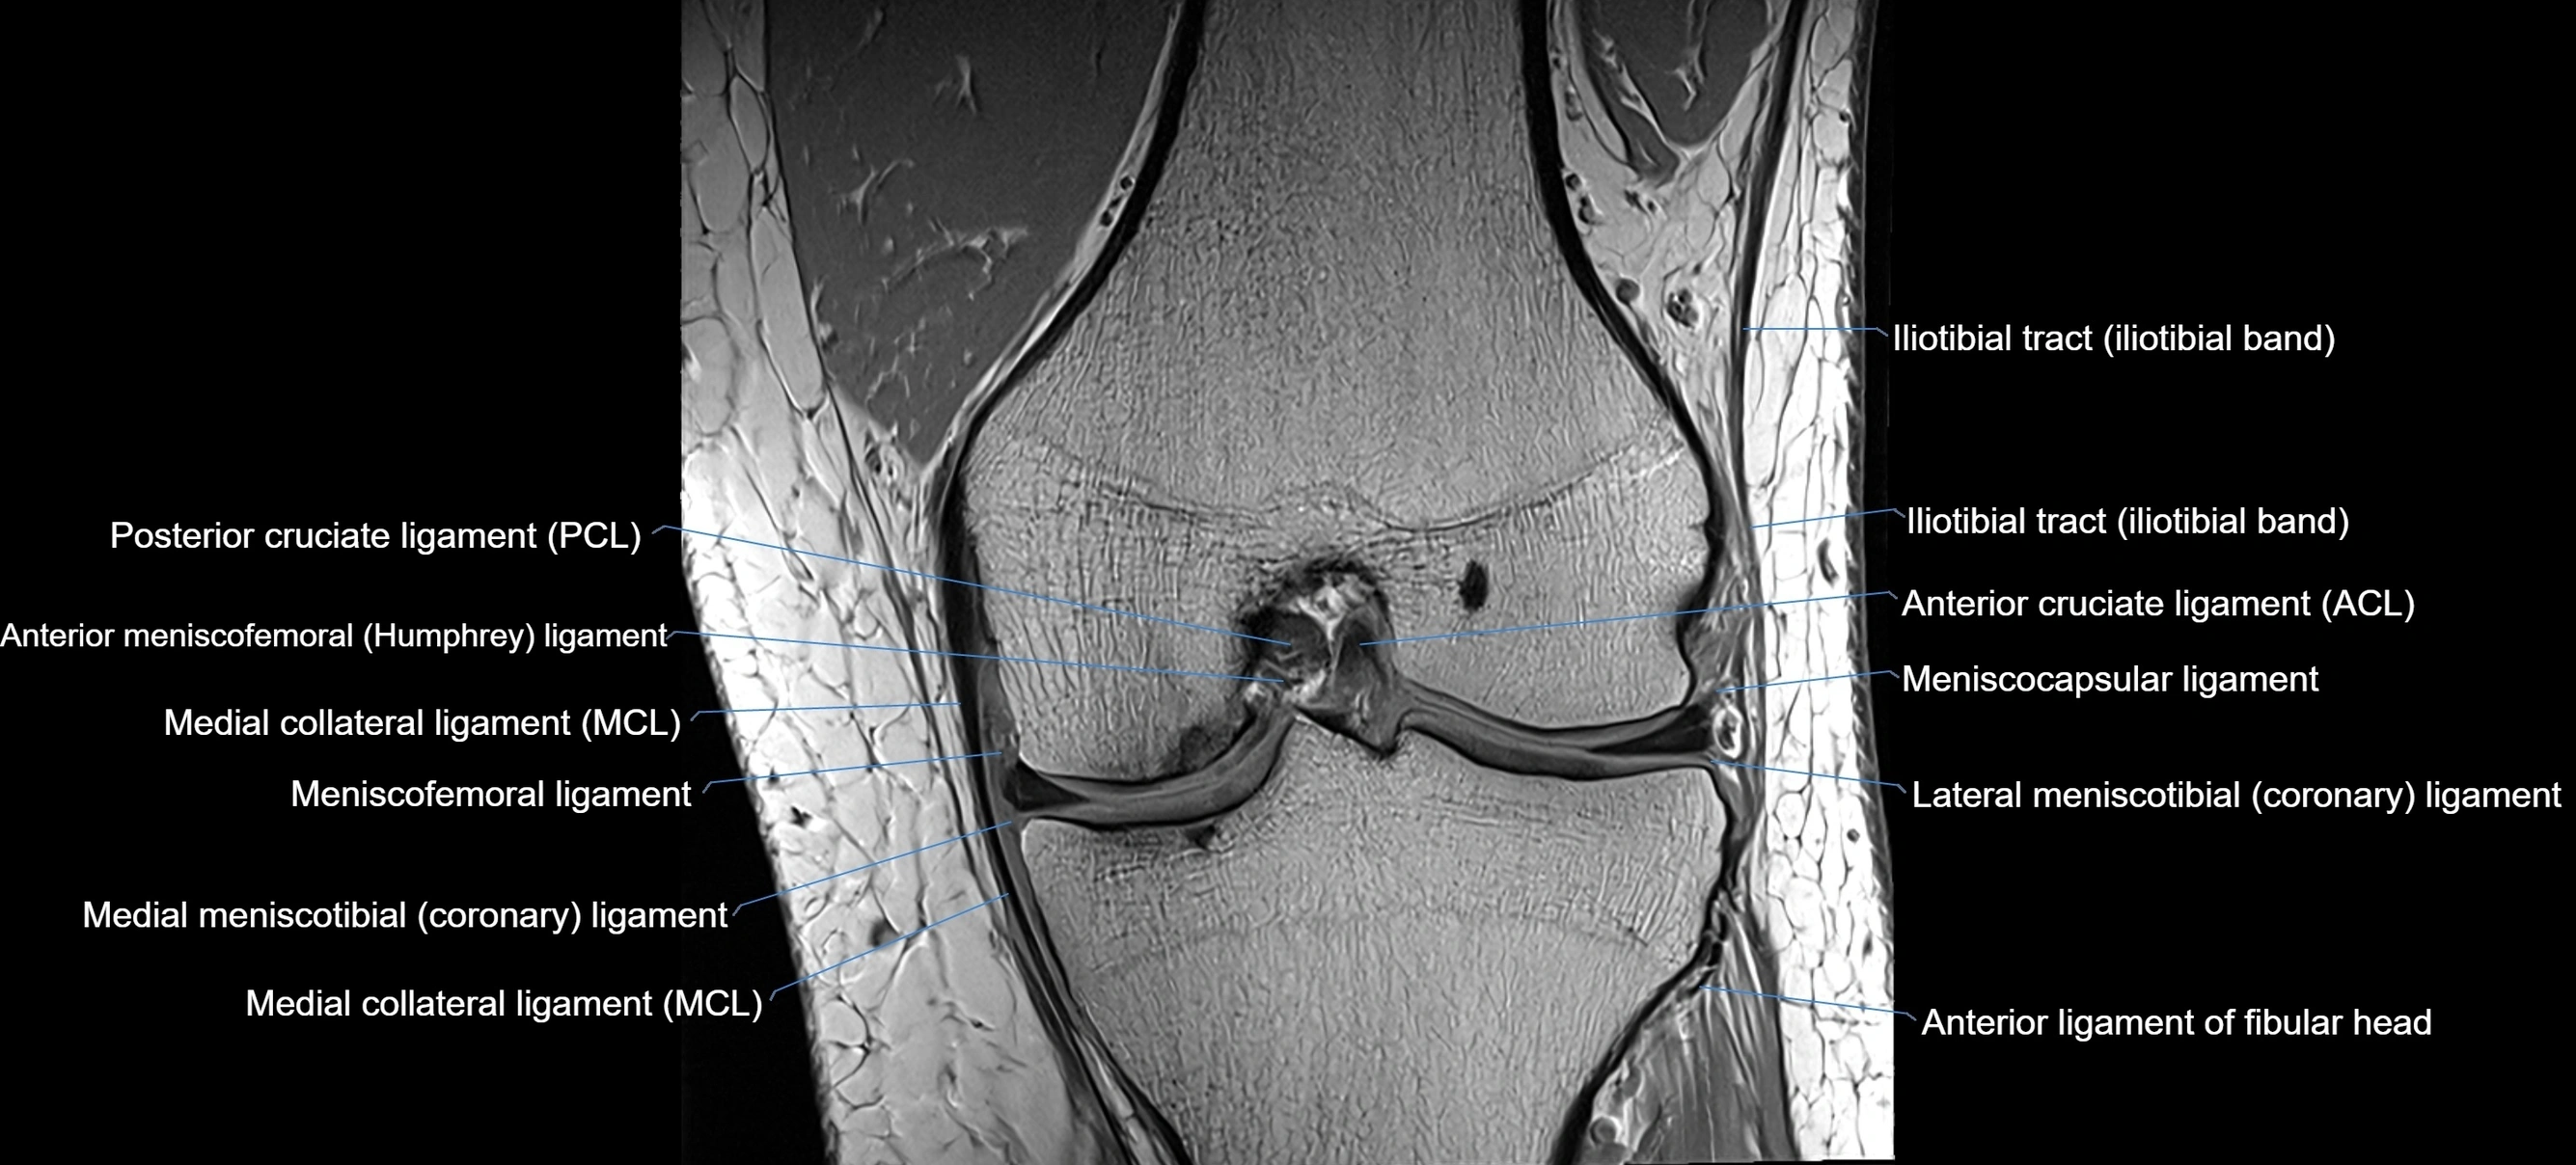

MRI images

image